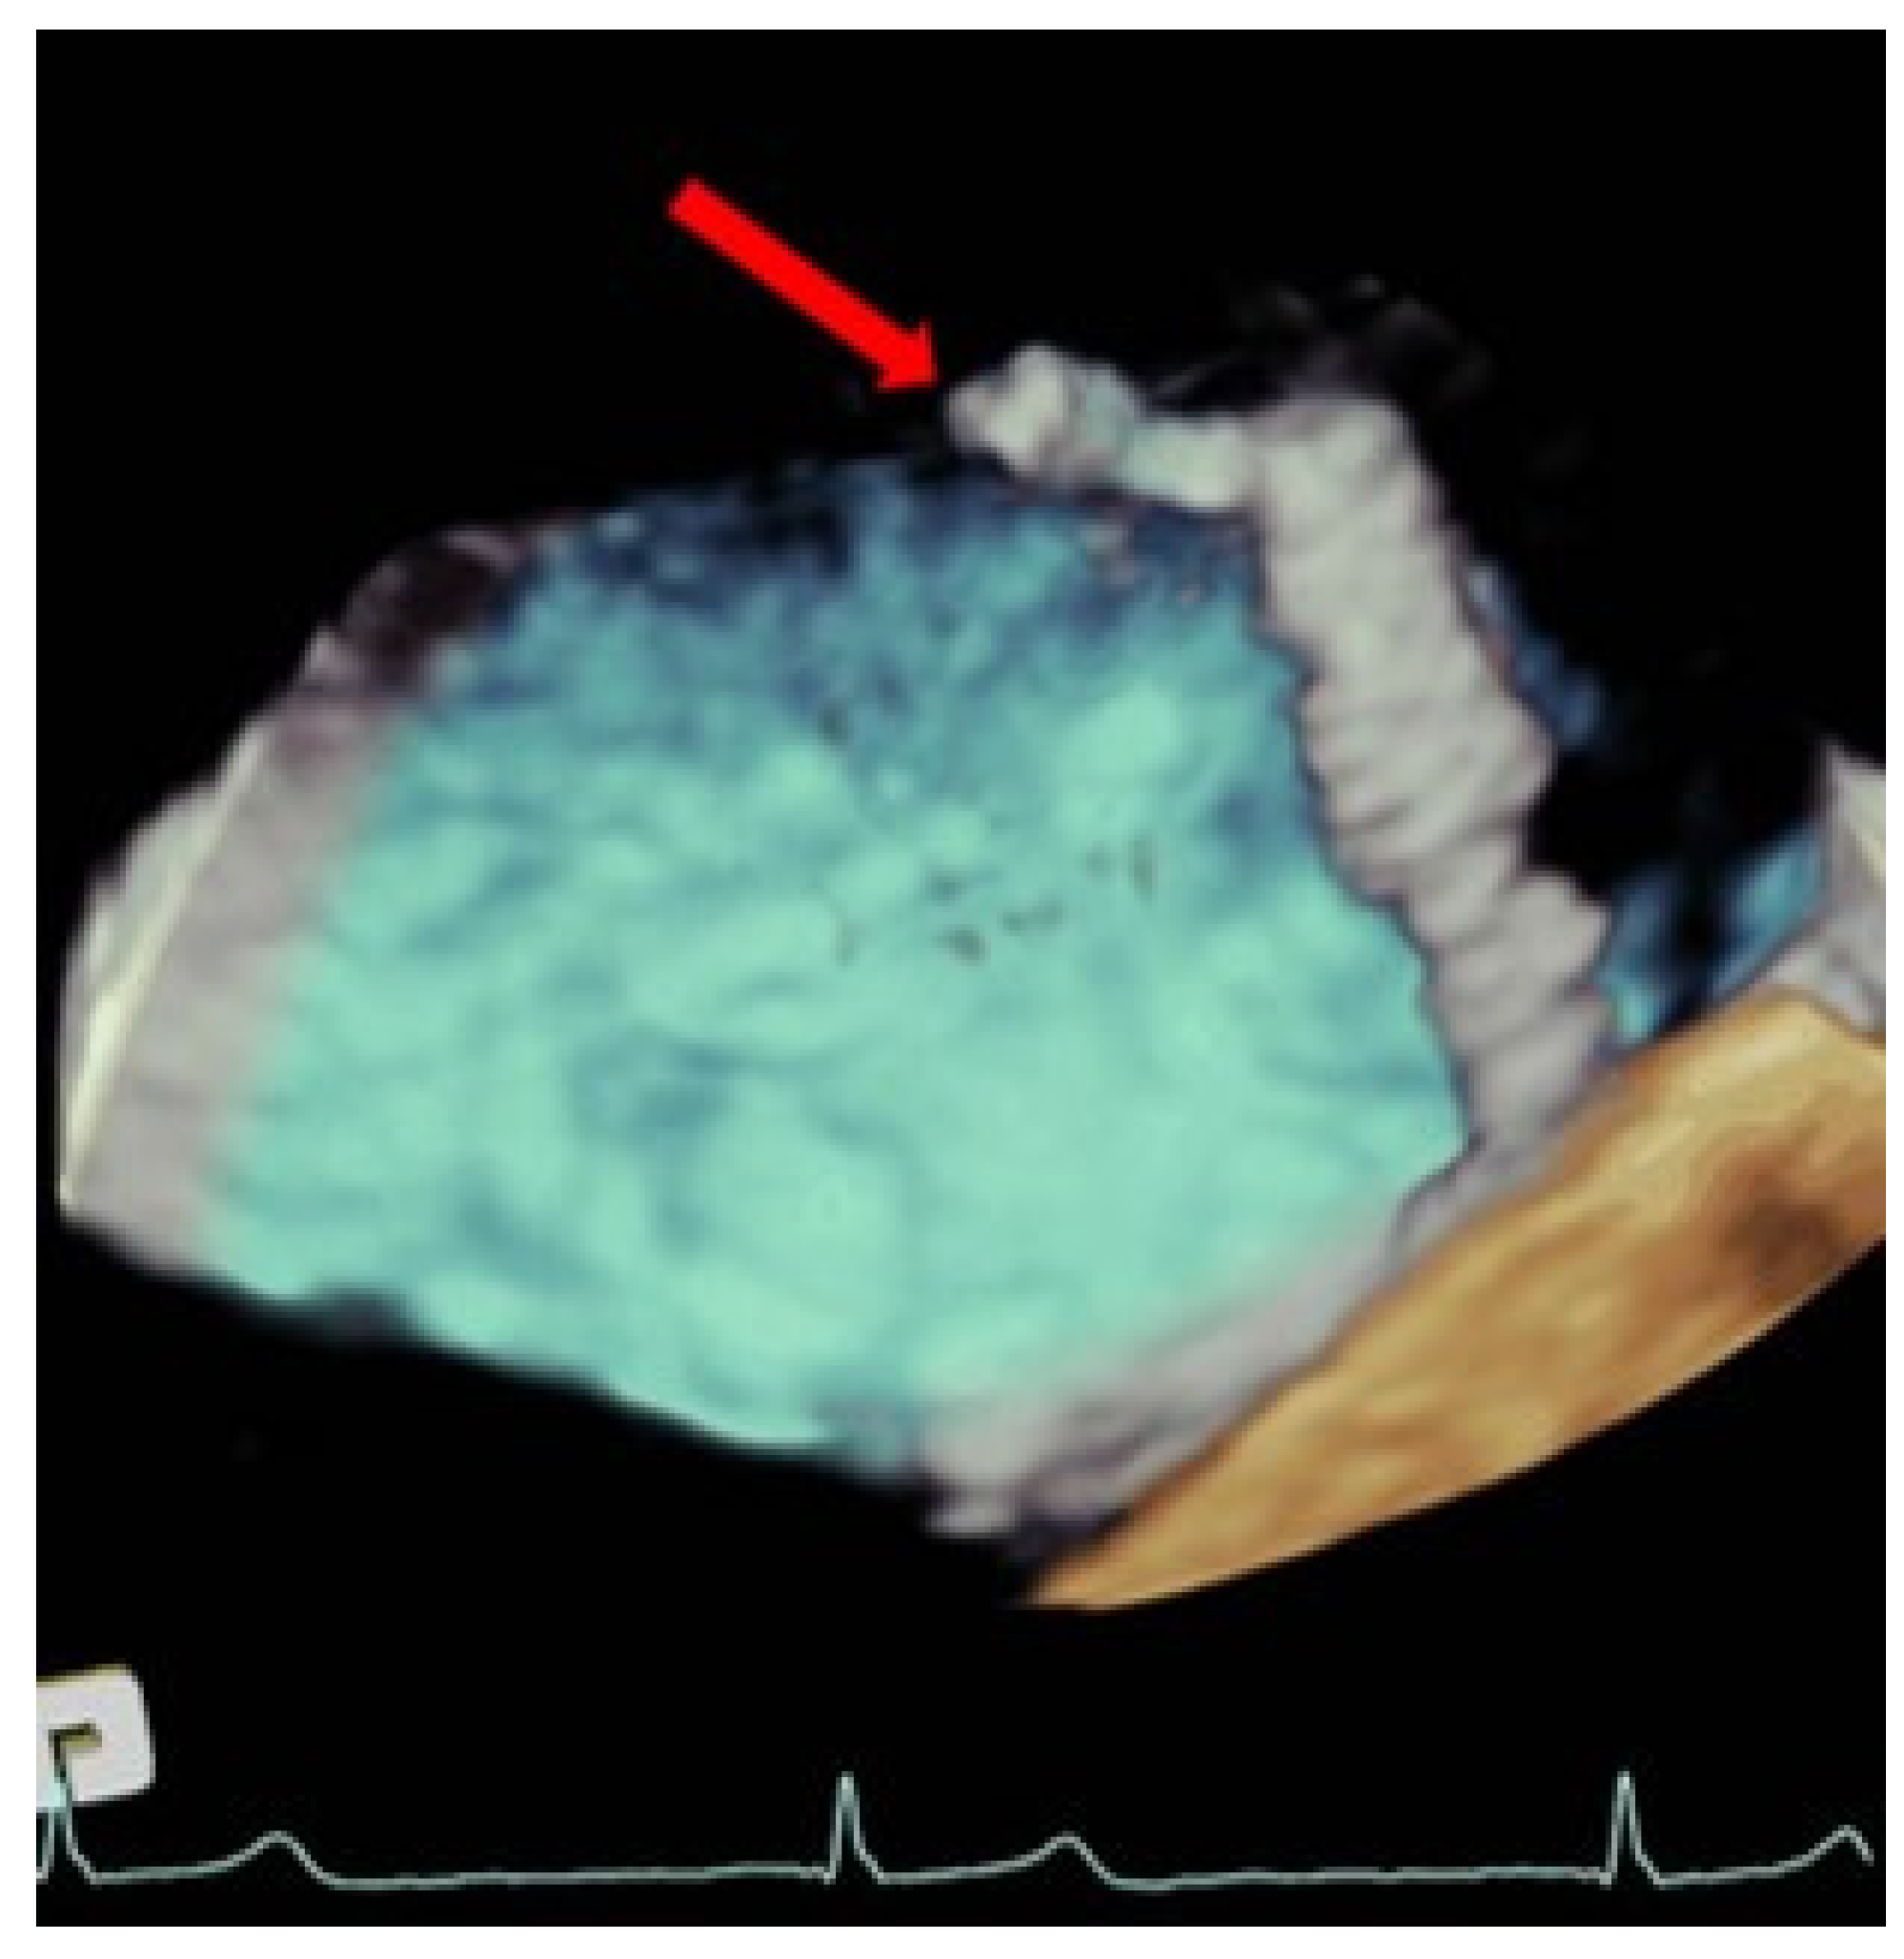

TEE allows for the assessment of the ASD, morphology, and size, it being superior to visualization through 3D-TEE. If the percutaneous closure of the ASD is necessary, the TEE is essential in guiding the procedure [27] (Figure 7).

Figure 7.

Persistent atrial septal defect. (Left) Three-dimensional transesophageal echocardiogram image showing a large atrial septal defect with tearing of the tissue through the transseptal puncture area (yellow arrow) from the left atrium. (Right): Two-dimensional transesophageal echocardiogram showing an Amplatzer device closing the iatrogenic atrial septal defect (red arrow).